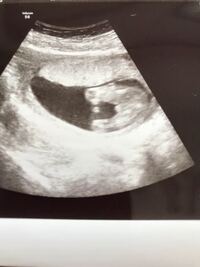

このエコー写真は女の子に見えますか?目を凝らすとスジが見えるのですが、女の子の印のコーヒー豆は3本線には見えないですか? 妊娠 締切済 教えて!goo エコー画像 性別について 週健診で突起があるため男の子8割と言われたエコー画像です おまたに3本線も見えるのですが、男の子だとするとこの3本線はなんの3本線なのでしょうか? 4週間前の健診では突起がなかったため女の子ぽいねーと言われました 24週3日(24w3d・女の子)|keee_8 さん(23歳) エコー写真撮影時のエピソード: 初めて顔がはっきりわかるエコー写真でした。こんなにもパパに似るものかと夫婦で笑い、お互いの家族に写真を撮る送りました。両親も自分たちの頃とは違ってよく顔がわかる

エコー写真 性別の見分け方 男の子女の子別エコー 妊娠週まとめてみました ママびよりウェブ これが 女の子の3本線 13週でエコーをとったのですが おし Yahoo 知恵袋 すべてのカタログ 美しい エコー 性別 間違い このエコー写真は男の子か女の子か分かりますか このエコー写真は男 妊娠 女の子のエコー写真 ©ママリ 女の子のエコー写真では股の部分に割れ目が見えることもあります。ただし、へその緒が写りこんでよく見えなかったり胎児が足を閉じていたりすることも考えられるため、一回の超音波検査では判断が難しい場合があります。 出典元 日本産科婦人科学会( 今日は独自に調査・お願いをして女の子のエコー写真を集めてみました! 色々なエコー写真を見ていると、これは女の子だ!というのも少しずつわかってきますので、ぜひ他の方の写真も参考にしてみてくださいね。 Contents 女の子の性別判定はいつから可能? 週数別女の子のエコー

エコー写真になります これが女の子の証 3本線というものでしょうか Yahoo 知恵袋